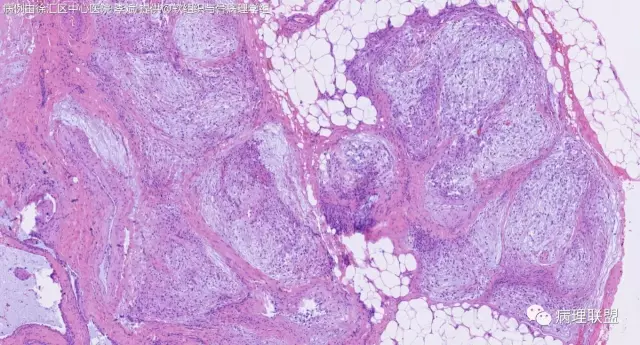

关节旁粘液瘤,肿瘤中间明显有腱鞘囊肿结构,又发生在关节处!强烈提示为关节旁粘液瘤,部分病例可以呈分叶结构!平时多加观察腱鞘囊肿囊壁常可见粘液变性!范围一广就成粘液瘤样。

@周泉 周老师您好,李斌老师第一个病例里细胞都是上皮样的包浆宽的,嗜酸,粘液瘤细胞细胞梭的星形的,所以我考虑是神经鞘的了,您觉得粘液瘤细胞也可以这种形态吗?

@左淑英 部分应该是组织细胞